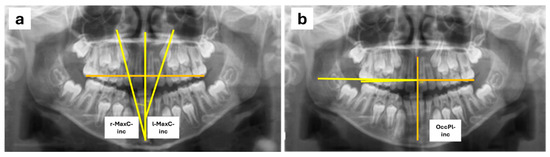

For the measurements, a reference plane was set up using the midline passing through the midpoint of the palatal suture and the anterior nasal spine. To assess MaxC-inc, the angle between the reference plane and a line following the longitudinal axis of the maxillary canines was measured (Figure 1a) following the Power–Short and Canut techniques [30,31]. For the measurement of OccPl-inc, the occlusal plane was defined by drawing a line passing through a point at the center of the occlusal surface of the permanent first maxillary molars or, if the permanent molars had not yet erupted, the second maxillary primary molars. A line perpendicular to the reference plane was drawn at the point where it intersected the occlusal plane on the right side of the patient, and the angle formed between this perpendicular to the midline and the occlusal plane was measured (Figure 1b). Also, right (r-) and left (l-) sides were evaluated.

Figure 1. Radiographic measurements conducted in orthopantomographies: MaxC-inc (a) and OcclPl-inc (b).